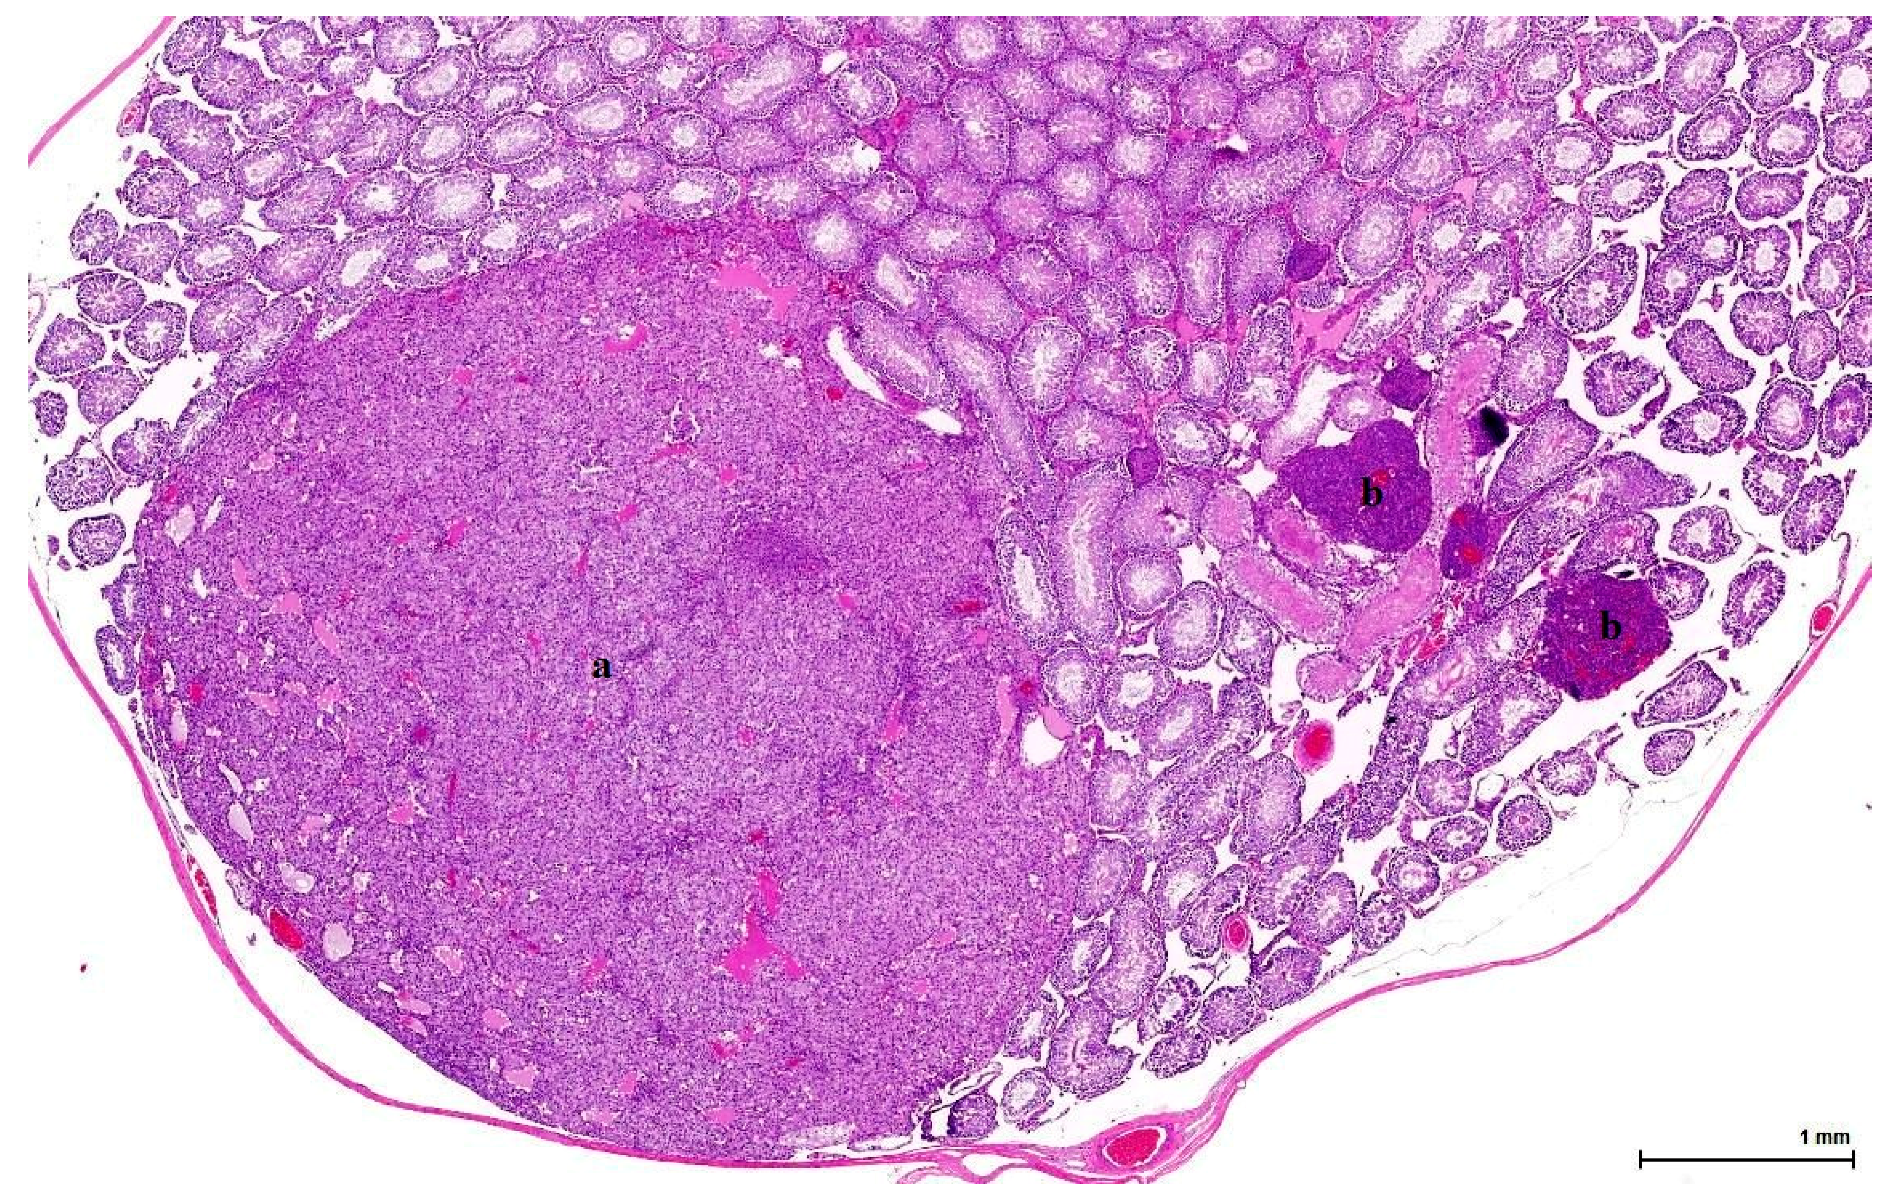

Figure 4. Ginkgo control Case 2 (Table 2). Dominant nodule (a) composed of pale eosinophilic cells; on the right (b), small nodules of basophilic cells (dark blue), measuring less than the three adjacent tubules (LCH of isolated finding). (H&E).

OTA controls from the 1989 NTP study show the same type of tumour as those exposed daily to OTA for many months in London in the 2000s. Disease was bilateral in 5/6 cases and in the standard transverse sections measured up to 13 mm, with one being larger than the other. The remaining testicular parenchyma is either normal, with active spermatogenesis, or atrophic, with calcifications within a few enlarged tubules. The non-tumoral section shows a few nodules of small basophilic interstitial cells, not distorting the normal architecture and measuring less than the three adjacent tubules (Figure 4).

In controls from the Ginkgo study, half of the cases show tumour on both slide sections (50% bilateral disease), either as one compact nodule or as multiple isolated or coalescent nodules, with solid and cystic architecture, placed in a normal or atrophic testis, with focal intratubular calcifications. The other half of the cases shows the same type of tumour, but on one section only (unilateral disease); the other section (non-tumoral) shows only a few nodules of interstitial cells between normal seminiferous tubules.

Histologically, LCH may be diffuse, focal or multifocal; the constituent cells are cytologically unremarkable, showing neither marked changes in size, nor pleomorphic or mitotically active nuclei [21]. This lesion has no expansive growth and does not distort or compress adjacent parenchyma. Based on this axiom, LCH was diagnosed as an accompanying lesion in only one OTA control case and in half of the Ginkgo control cases as small nodules, measuring fewer than three adjacent tubules, usually multiple, in an otherwise normal (three cases) or atrophic (one case) testis. By contrast, adenomas were diagnosed in all cases (OTA and both controls) as large, expansile masses, solitary or multiple.